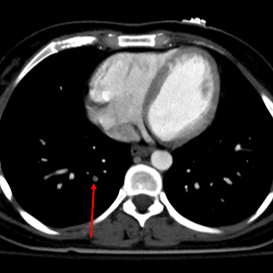

Trauma CT shows subtle right lower lobe PE. This should be easy to pick up on conventional CT.